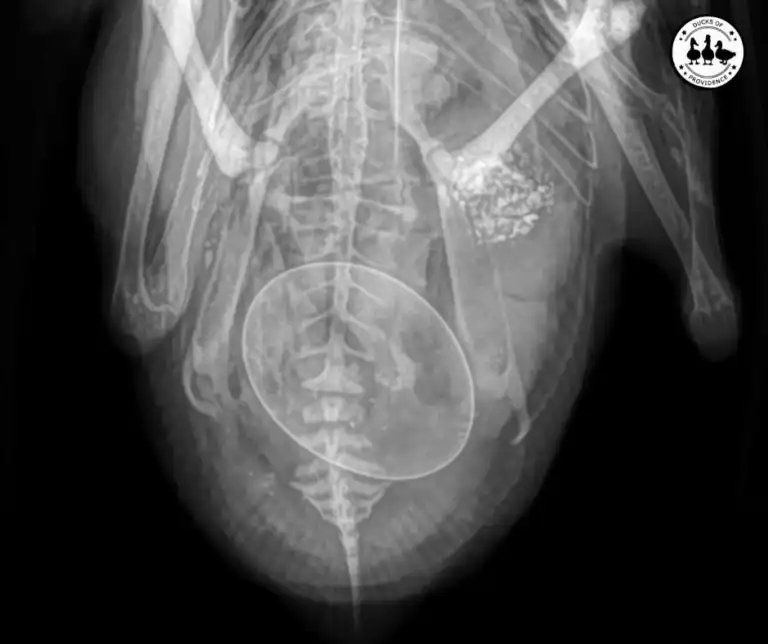

How We Treated Our Egg-Bound Duck Penny (Case Study)

Egg-binding is one of the most serious reproductive emergencies in laying ducks. When a duck cannot pass an egg normally through the oviduct, the condition can quickly become life-threatening if not addressed promptly. Early recognition and veterinary support are critical,…